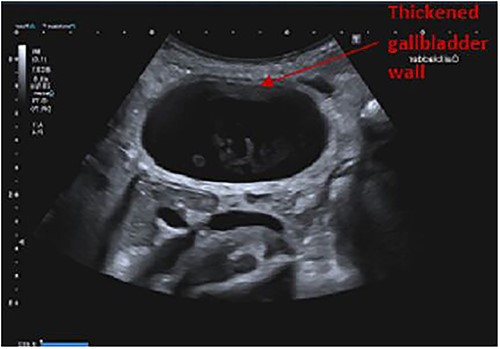

Findings on abdominal ultrasound included a distended gallbladder with thickening of the gallbladder wall up to 7 mm. Definite cholelithiasis was not noted but the gallbladder contained sludge. No dilatation of the intrahepatic or extrahepatic biliary tree was identified (Figs 1 and 2).